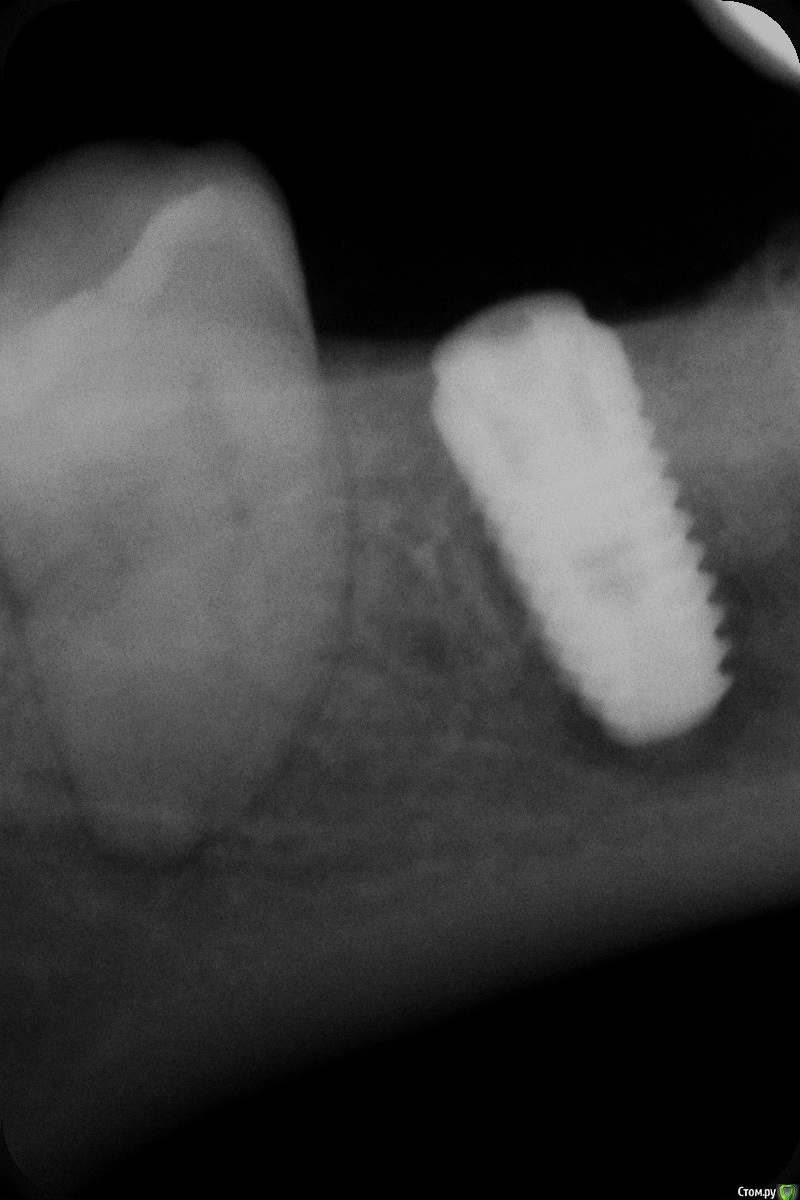

johniola Опубликовано 19 июля, 2016 Поделиться Опубликовано 19 июля, 2016 (изменено) История такая! Месяцев 7 назад удалили 47зуб,была вылущена киста и уложен аллографт (корея).Через 6 месяцев получили кость и установили имплант 4.3 на 10 мм.Через неделю у пациента начались боли и имплант был удалён.Какие мысли ?Вечный вопрос почему? Сверление свежими фрезами на 600 оборотов.Торг при установке около 30. Изменено 19 июля, 2016 пользователем johniola 1 Ссылка на комментарий

johniola Опубликовано 20 июля, 2016 Автор Поделиться Опубликовано 20 июля, 2016 первый снимок это сразу после операции либо когда прошло неделю?первый снимок сразу после установки,второй через неделю Ссылка на комментарий

kamranchick Опубликовано 20 июля, 2016 Поделиться Опубликовано 20 июля, 2016 Заглушке странная какая то))) как будто не плотно сидит)) Ссылка на комментарий

johniola Опубликовано 20 июля, 2016 Автор Поделиться Опубликовано 20 июля, 2016 Заглушке странная какая то))) как будто не плотно сидит))заглушка от другой модели импланта,подходит и к этому. Просто на этих имплантах заглушка идёт отдельно,у меня их много в коробочке,вот и эта попалась под руку Ссылка на комментарий

Fibez Опубликовано 20 июля, 2016 Поделиться Опубликовано 20 июля, 2016 Джохниола (блин, надеюсь правильно пишу), причина может быть любая. От "запихали" какую-нить гадость из полости рта, до какой-нить не выявленной общесоматической проблемы. Никто Вам ничего конкретного не скажет. По описанию протокола и снимку (сомнительного качества) ничего необычного не видно. Про слюну на поверхности винта... Был у меня с полгода назад пациент на 3.5 и 3.7 А ася была неопытная. Совсем. А пациент ну очень языкастый. Так он мне оба импланта в слюне вымочил целиком и еще и языком по ним поелозил как следует. В результате всё зажило как обычно. Ссылка на комментарий